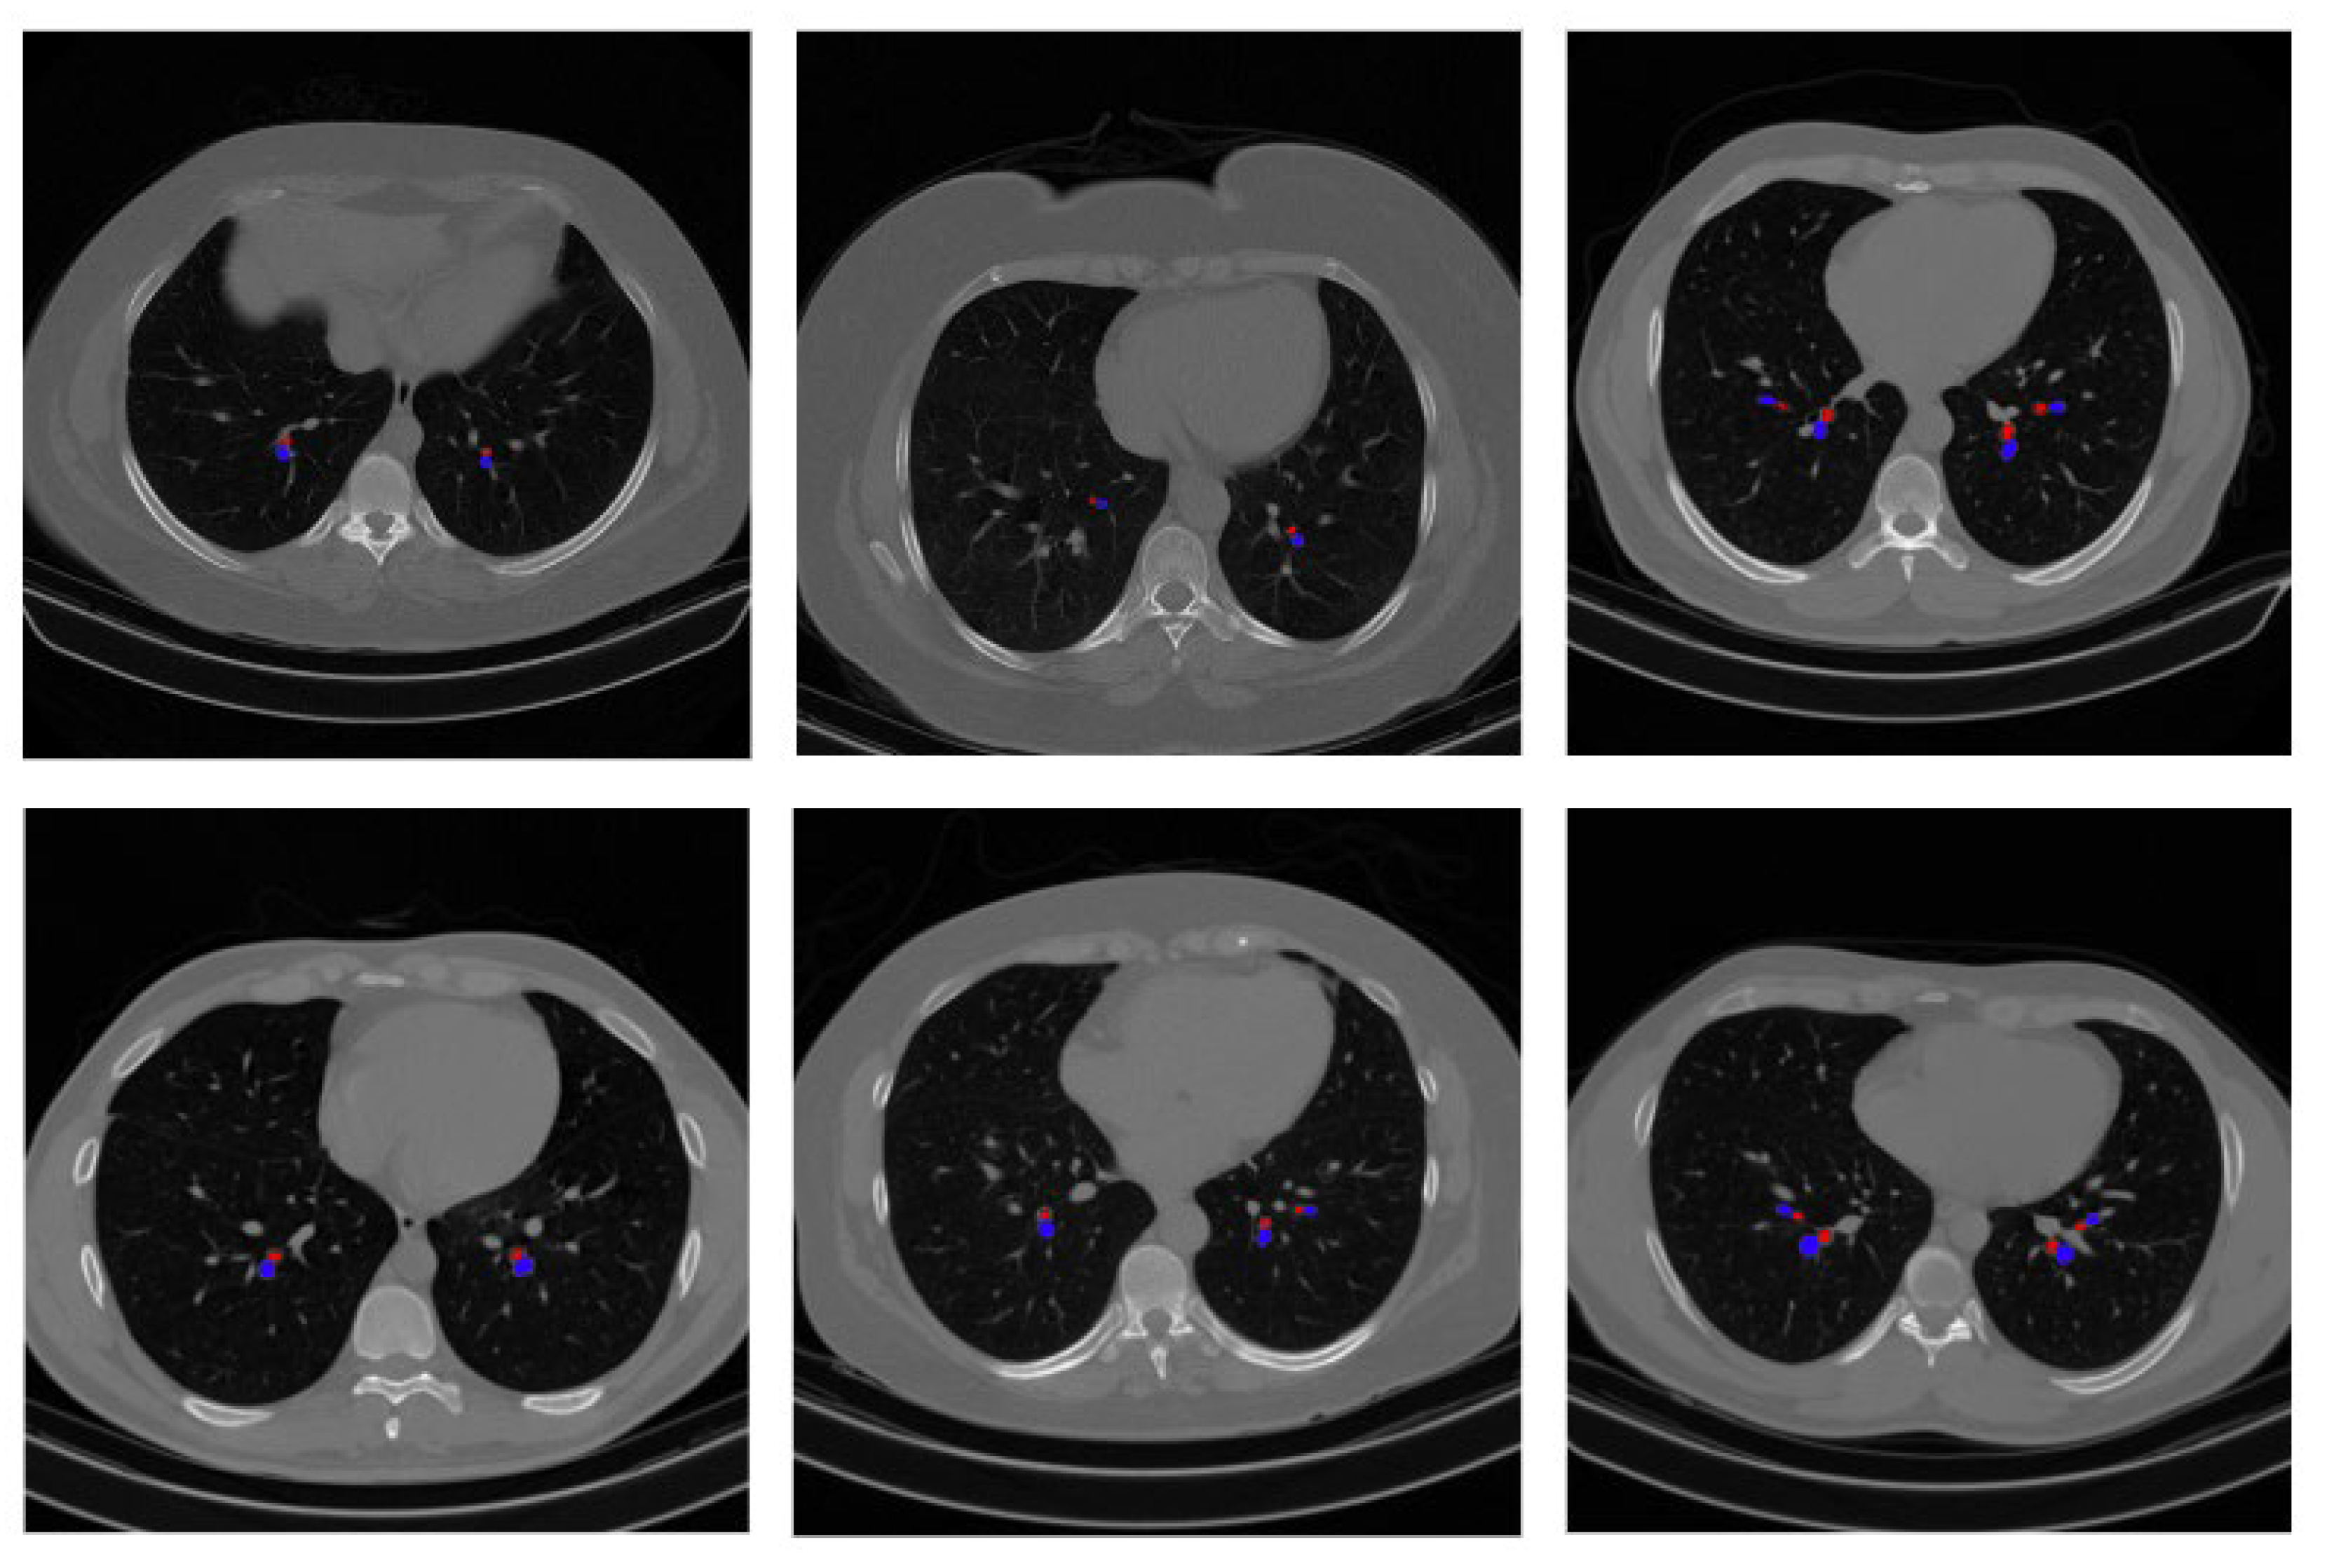

3.6. BA Pair Extraction

4.1. Performance Validation of the Proposed Approach